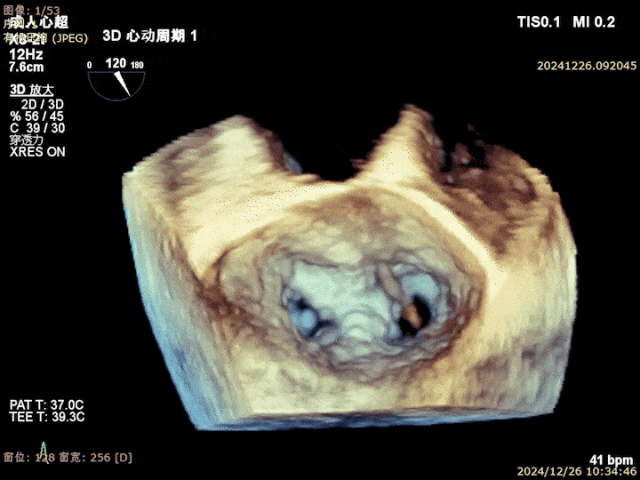

患者重度(4+)二尖瓣反流、并伴有P2区瓣叶脱垂及部分腱索断裂、且外科治疗风险极高,术中团队借助DragonFly™系统的高精度操控特点,精准解决了患者瓣叶脱垂问题,并仅凭一枚XW0612长宽二尖瓣夹即圆满完成手术。术后患者二尖瓣反流显著降低至微量,治疗效果满意。此次,TEER手术的成功,是大医一院结构性心脏病团队在二尖瓣微创介入治疗领域新的突破,将为更多瓣膜病患者提供一种更安全有效、更微创的治疗手段,从而解除病痛,改善预后。

关闭二尖瓣夹

二尖瓣夹释放后评估